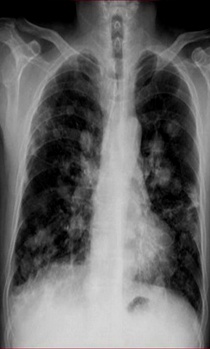

滿肺可見“滿天星”,根據(jù)公式診斷肺轉(zhuǎn)移瘤